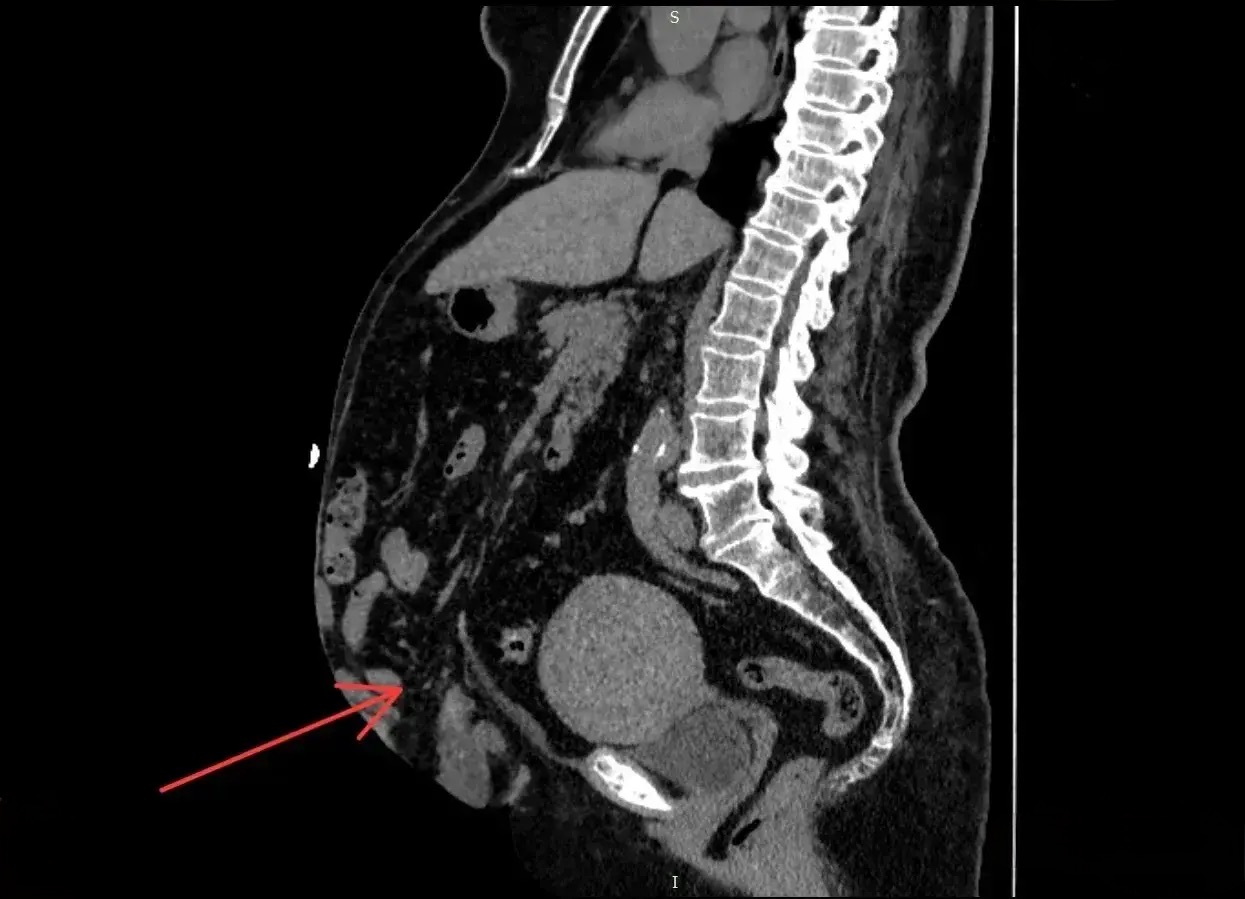

Компьютерная томограмма показала, что грыжа занимает 41% объёма брюшной полости — такое состояние называют потерей домена. «В год мы оперируем до 40 пациентов с послеоперационными грыжами, из них гигантские встречаются у одного-двух человек. Для хирурга это не самая простая операция, требуется опыт, отличное знание процедуры. Кроме того, нужна тщательная предоперационная подготовка, чтобы подобрать нужный вид оперативного вмешательства», — отметил заместитель главного врача по хирургической работе Вячеслав Смирнов.